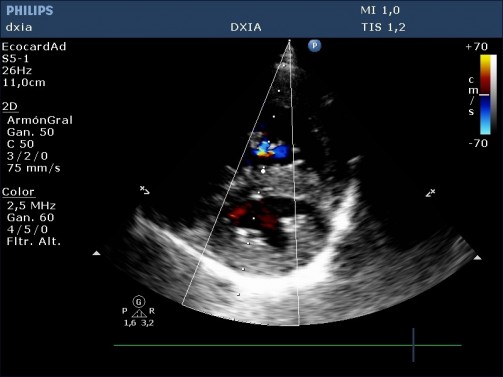

Predominancia de cámaras derecha, con marcada dilatación de estas (AD y VD)

Leve engrosamiento de cúspides de la VT

Insuficiencia tricuspídea excéntrica de alta velocidad (4,2 m/seg)

Hipertrofia moderada de pared libre del VD y del SIV

No aplanamiento septal

Arteria pulmonar dilatada pero perfil flujo pulmonar debido a: